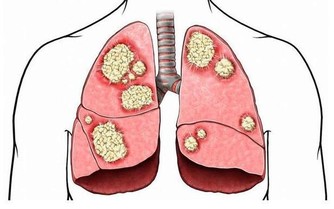

• 陰虛火旺者好吃

凡屬陰虛火旺、目赤內熱者,或患有癰腫瘡癤、肺炎、肺膿腫、肺結核、胃潰瘍、膽囊炎、腎盂腎炎、糖尿病、痔瘡者,都不宜長期食用生薑。